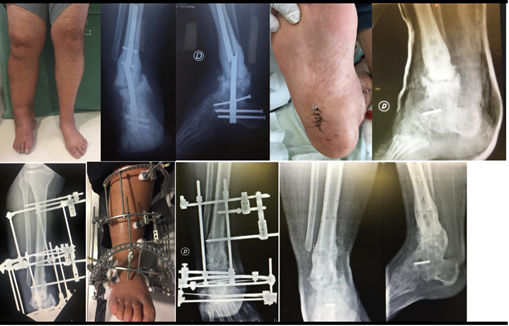

Caso 2

Varón de 57 años, trabajador rural, antecedentes patológicos de hipertensión, obesidad y enfermedad de Charcot-Marie-Tooth, portador de una secuela tardía de una osteotomía realizada en su tibia izquierda que requirió cambio de implante y artrodesis tibio calcáneo astragalina. A los 10 meses de evolución presenta rotura del nuevo implante a nivel del foco de pseudoartrosis. En ese momento valoramos el paciente, presentándose con una claudicación para la marcha por dolor y tumefacción localizado en miembro inferior izquierdo, a nivel de tobillo, provocando limitación para trabajar y necesidad de un bastón para deambular. Del examen físico se destacaba una desviación del tobillo y retropié en varo. El pie presentaba una deformidad en cavo desde la infancia. A nivel de la deformidad no se observaba movilidad y no presentaba dismetría. La piel se encontraba fina, pero sin lesiones. Los pulsos estaban presentes y en el examen neurológico del pie destacaba una alteración de la sensibilidad profunda. Al analizar las imágenes se observaba una pseudartrosis de la tibia distal hipertrófica desviada en varo con un implante endomedular roto. Además, la articulación tibioastragalina se observaba artrodesada acorde con la historia previa. Se realizó, en un primer tiempo, el retiro del implante para evitar que este dificultara la colocación del aparato circular. En un segundo tiempo, se colocó el montaje de fijadores circulares con bisagras y motor siguiendo la deformidad. La duración de la cirugía fue de 90 minutos. (Figura 3 y 4)

En ambos casos la complicación ocurrida fue la intolerancia a los alambres y schanz (Pin), que se trató con antibióticos vía oral y lavados frecuentes.

El período de seguimiento fue de 12 meses, logrando la consolidación ósea, sin infección, con retorno laboral a los 8 meses de la cirugía, sin limitaciones ni dolor y con persistencia de leve deformidad residual. Los pacientes se encontraban satisfechos con el resultado terapéutico.